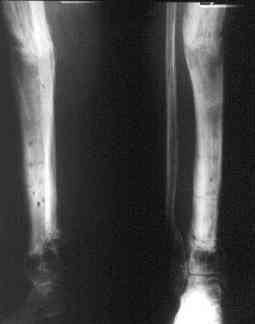

Может, данное наблюдение поможет в принятии решений в подобных ситуациях.

Огнестрельный дефект костей и передней группы мышц, поступил с юнилатеральным аппаратом, стабильность плохая, из раны обильное гнойное

отделяемое. #1;#2. Стержневой апп. снят, наложен апп. Илизарова, дренажно-ирригационная система промывки раны. #3; #4. После стихания инфекции,

исправлена ось и возмещен дефект. В результате восстановление тыльной флекcии стопы и функции конечности. #9;#10;#11